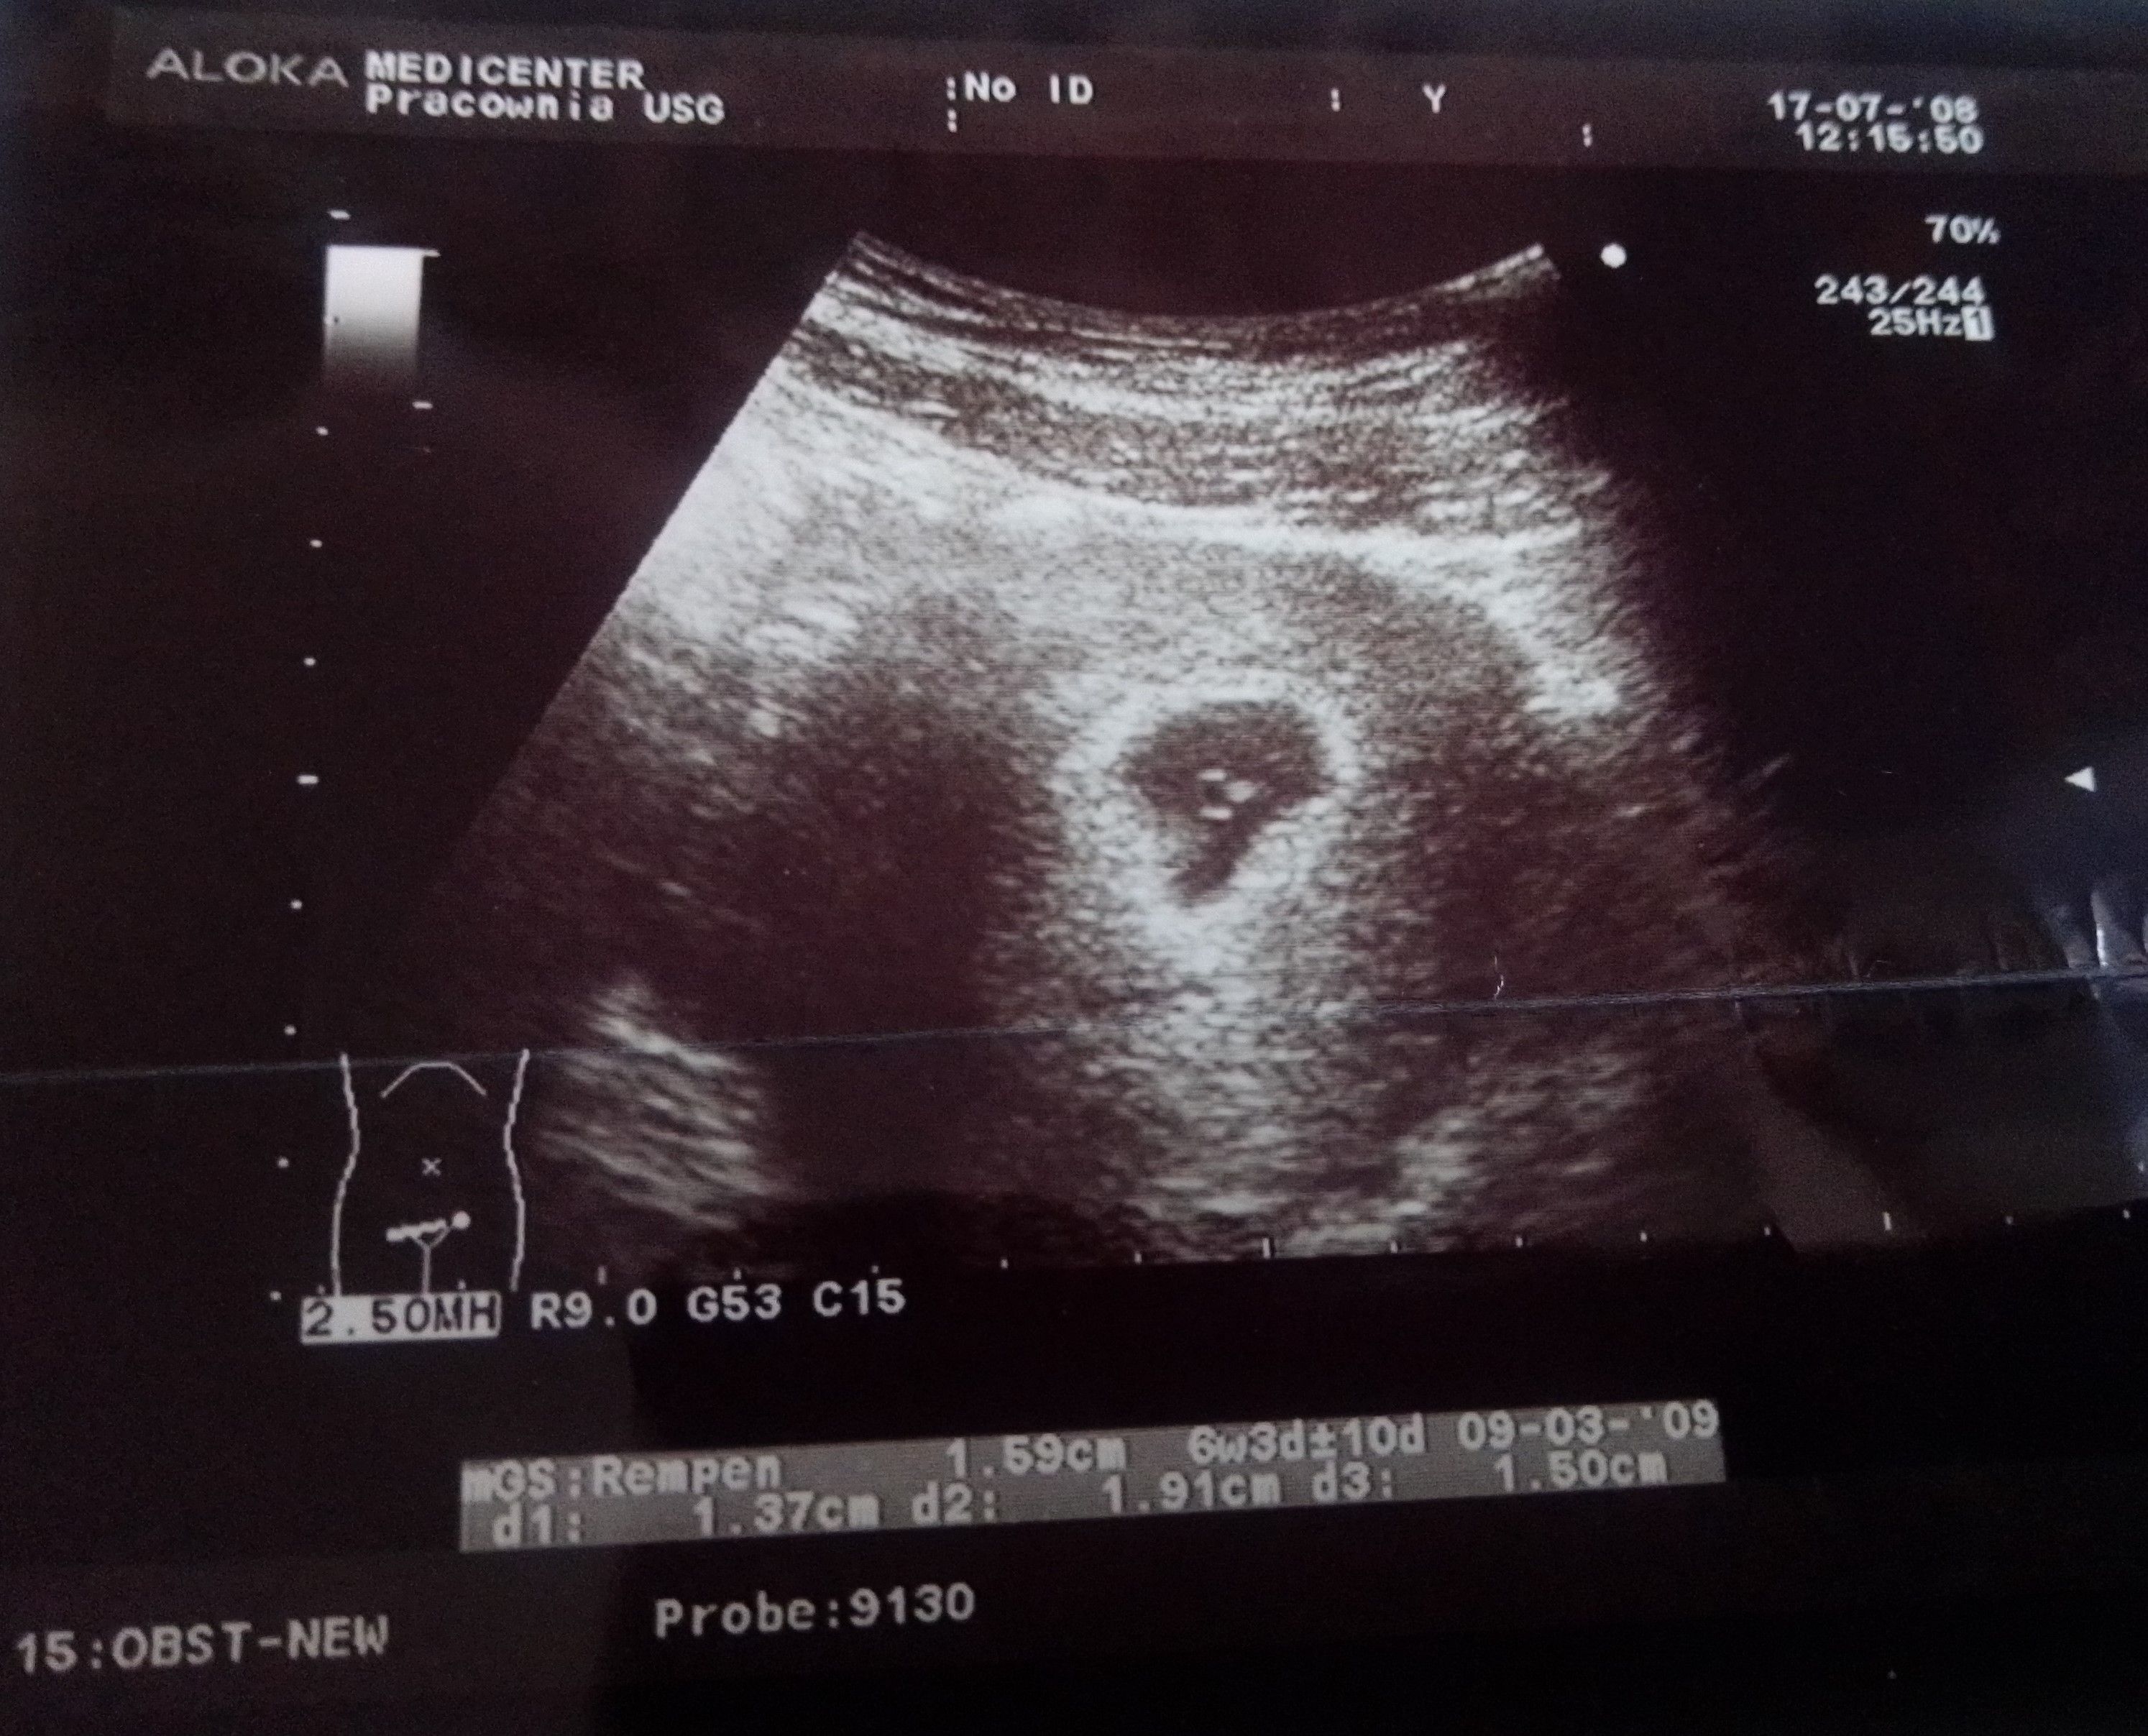

Podczas USG jamy brzusznej doktor zatrzymał się w miejscu na wysokości jajnika prawego i zamarł.. Spytałam co Pan widzi? Czy wszystko w porządku? Usłyszałam : nie jest w porządku, musi mieć Pani natychmiast operacje ponieważ na prawym jajniku ma pani torbiel czekoladowa wielkości pomarańczy!! Średnica 12 cm.